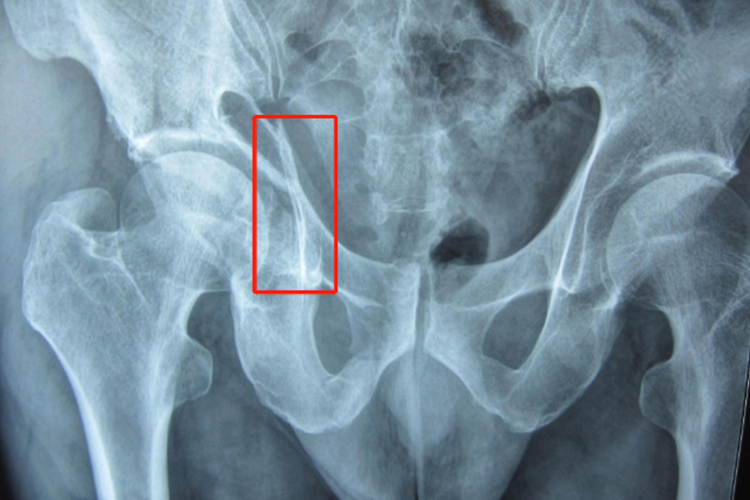

髋臼骨折以疼痛、畸形和功能障碍为主要表现,有时可发现大转子部位出现肿胀、瘀斑和压痛,通过影像学检查可见髋臼骨折处有明显断裂,与健侧形成鲜明对比。